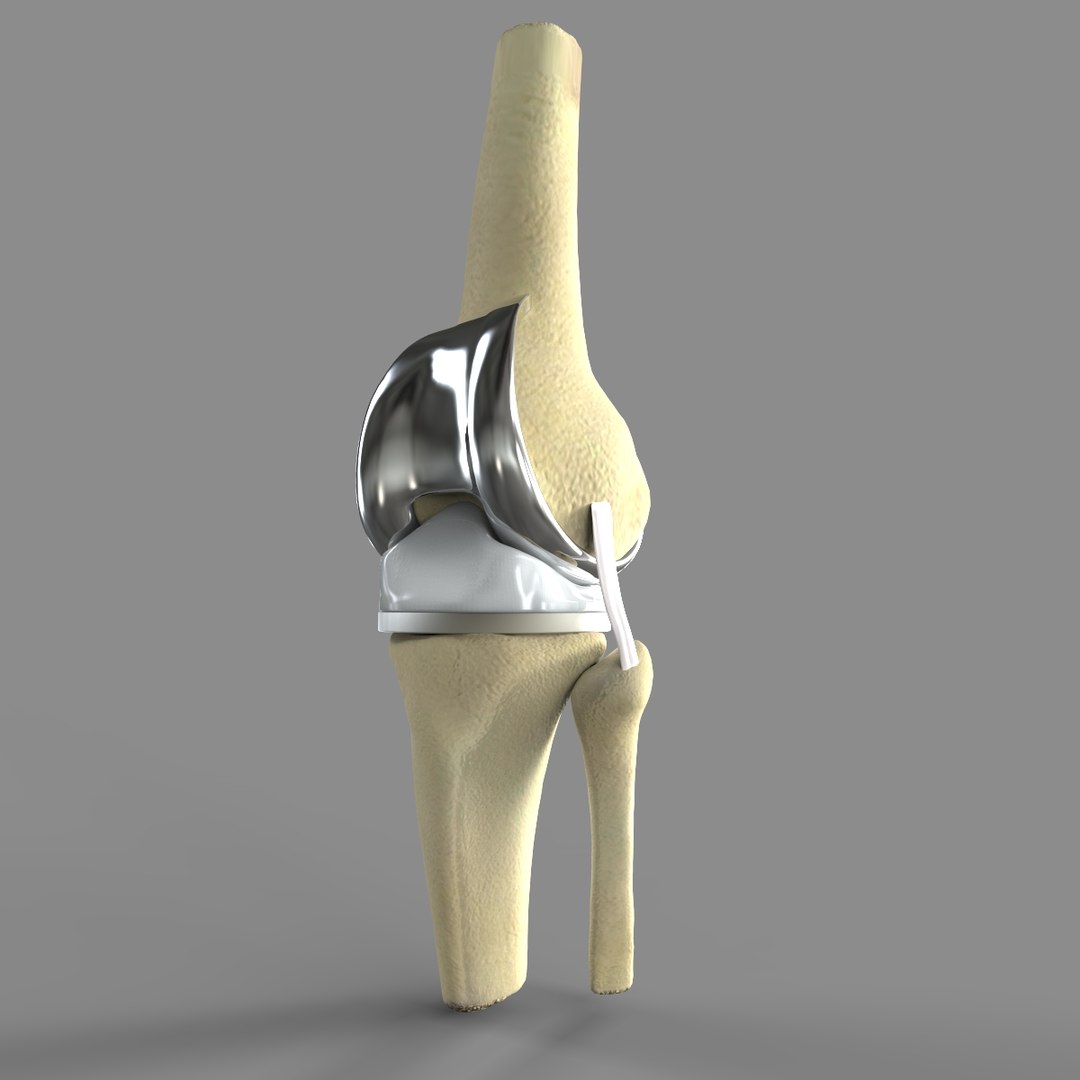

Knee 3D Model $60 - .c4d - Free3D

www.turbosquid.comknee turbosquid

www.turbosquid.comknee turbosquid

膝盖3D模型 - TurboSquid 607910

Knee Joint 3D Model | CGTrader

www.cgtrader.comknee cgtrader science

www.cgtrader.comknee cgtrader science

fity.club3D Knee Replacement Model - TurboSquid 1520233

fity.club3D Knee Replacement Model - TurboSquid 1520233

www.turbosquid.comturbosquid maya anatomy implant